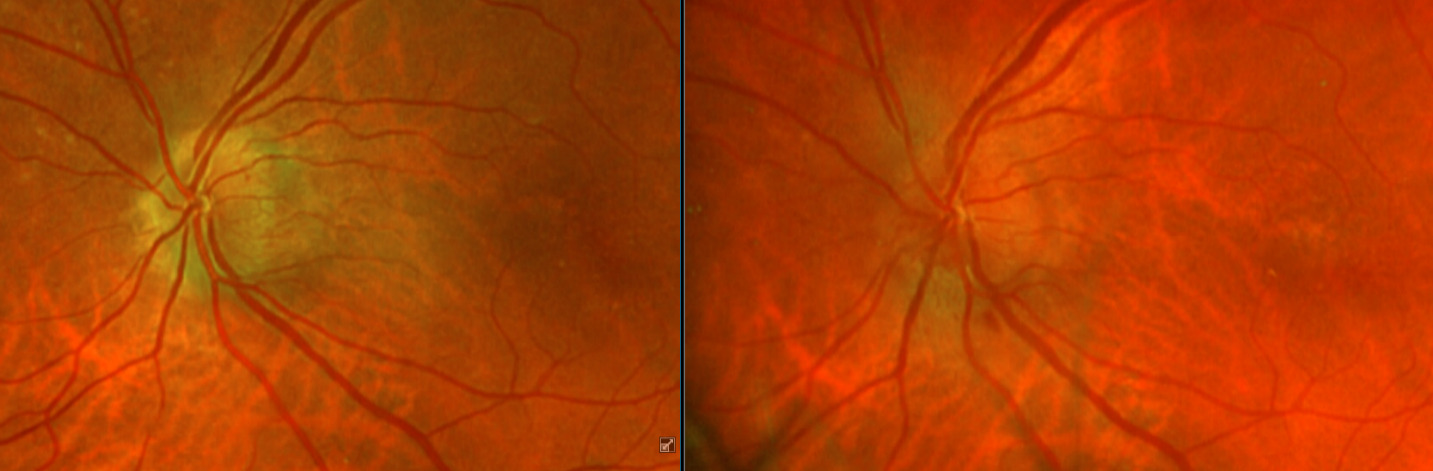

After additional testing was completed, and comparison of previous photos were conducted, it was determined that the patient had not only optic disc drusen, but also possible bilateral amiodarone optic neuropathy. The photos 4 months apart shows increasing pallor in the left eye and a blood vessel at 7 o’clock that did not look obscured initially but was evidently more pronounced on the follow up when comparing the initial and follow-up photos. This shows the importance of quality serial fundus photography.

Right image is original exam with inferior hemorrhage. Left image is 4-month follow-up visit. Resolution of the hemorrhage is seen, but atrophy of the disc overall should be noted. Vessel at 7 o’clock should also be noted. It appears much more pronounced than on initial visit.